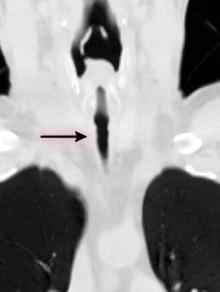

Anillo radiopaco formado por ganglios aumentados. El centro radiotransparente lo constituyen tráquea y bronquios centrales. Más frecuente en Tb y linfoma